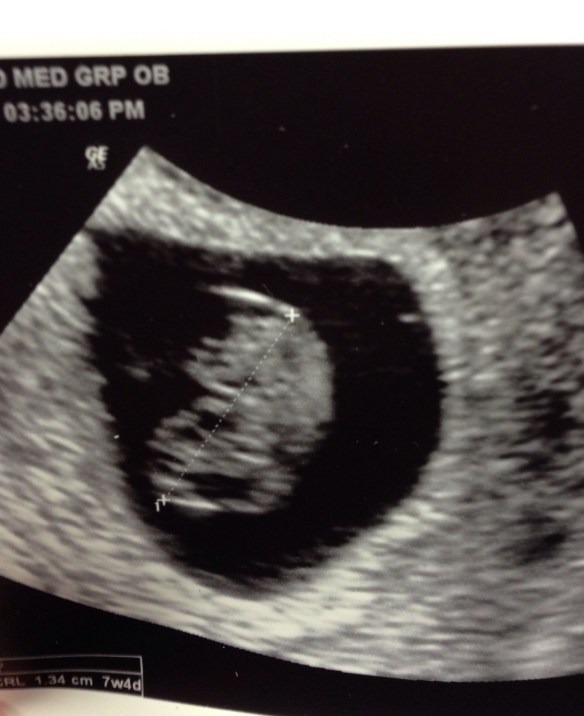

If you missed my Facebook announcement, I’m pregnant! For a few weeks we’ve been sharing the news with family and friends as we see them. And some of them have been sharing it with others. And that is great because this little life deserves to be celebrated!

I’m only 9.5 weeks, but feeling nauseous frequently, which isn’t fun but is a good pregnancy sign. Some people wait until 12 weeks when the first trimester is over to announce their pregnancy. They wait until they’re out of the “danger zone” of when miscarriage is most possible. But why? To avoid some kind of embarrassment of announcing, miscarrying, and then having to explain it? While I don’t think that would be embarrassing because miscarriage isn’t anyone’s fault and usually has no reason. But it isn’t easy to explain the situation. It’s uncomfortable if you run into a friend at the store who heard the first announcement, but not about the miscarriage, and starts to ask about the pregnancy.

So, fourth time around now, almost as soon as we knew I was pregnant we told our families. We celebrated. We prayed. We already love this little one. We are thanking God for another precious miracle and trusting Him to keep this baby safe and healthy inside me until His perfect timing to deliver.